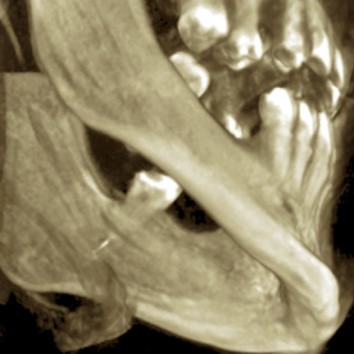

The patient’s symptoms and the close proximity of the broken instrument to the mandibular canal seen in panoramic radiography suggested that the broken endodontic instrument was in contact with the IAN. To confirm this diagnosis, CBCT examination was undertaken, and clearly showed the broken instrument in the periapical area of the mandibular left third molar and that the instrument was inside the mandibular canal. The result was the same as the panoramic examination, broken instrument was noted in the left mandibular canal Figure 3a, Figure 3b.

Figure 3a.CBCT surface examination broken endodontic instrument lodged in the mandibular canal.